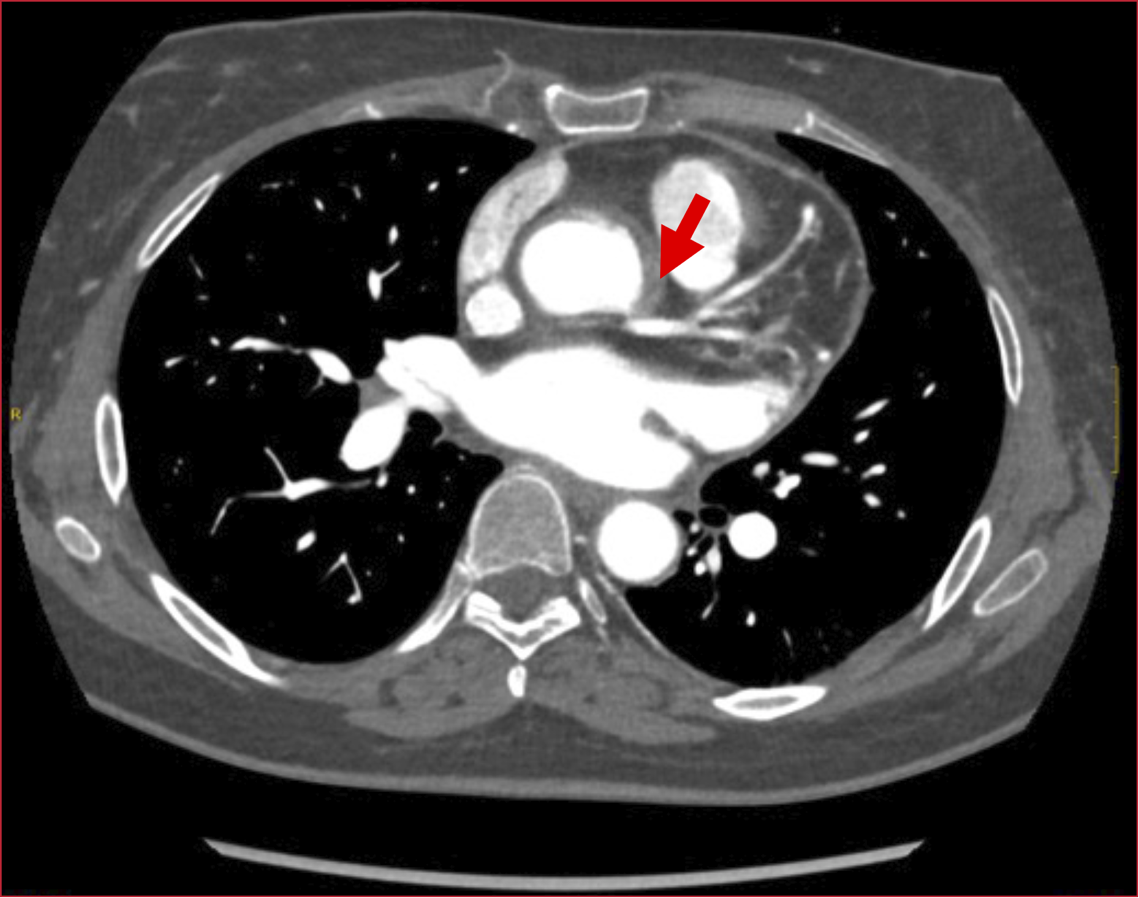

condición aórtica concomitante. La tomografía mostró (Figura 2):

• Signos de aortitis, se visualizó el

engrosamiento concéntrico de la pared vascular aórtica con tenue hiperdensidad

que sugiere compromiso inflamatorio.

• Un defecto de repleción en el origen de

la arteria coronaria derecha con flujo distal, así como estenosis en el origen

del tronco coronario izquierdo con flujo distal.

la arteria subclavia izquierda y, también, en el origen de la arteria ilíaca

común izquierda, con repermeabilización distal de ambas.

• Estenosis en el origen de la arteria

renal izquierda con buen flujo posterior.

• Un marcado aumento del calibre del

tronco arterial pulmonar, de hasta unos 42 mm, que sugiere hipertensión

pulmonar.

• Un leve engrosamiento pericárdico

ligeramente hiperdenso, en posible relación con pericarditis.

Figura 2. Aortitis. Estenosis del tronco coronario Izquierdo con flujo distal.